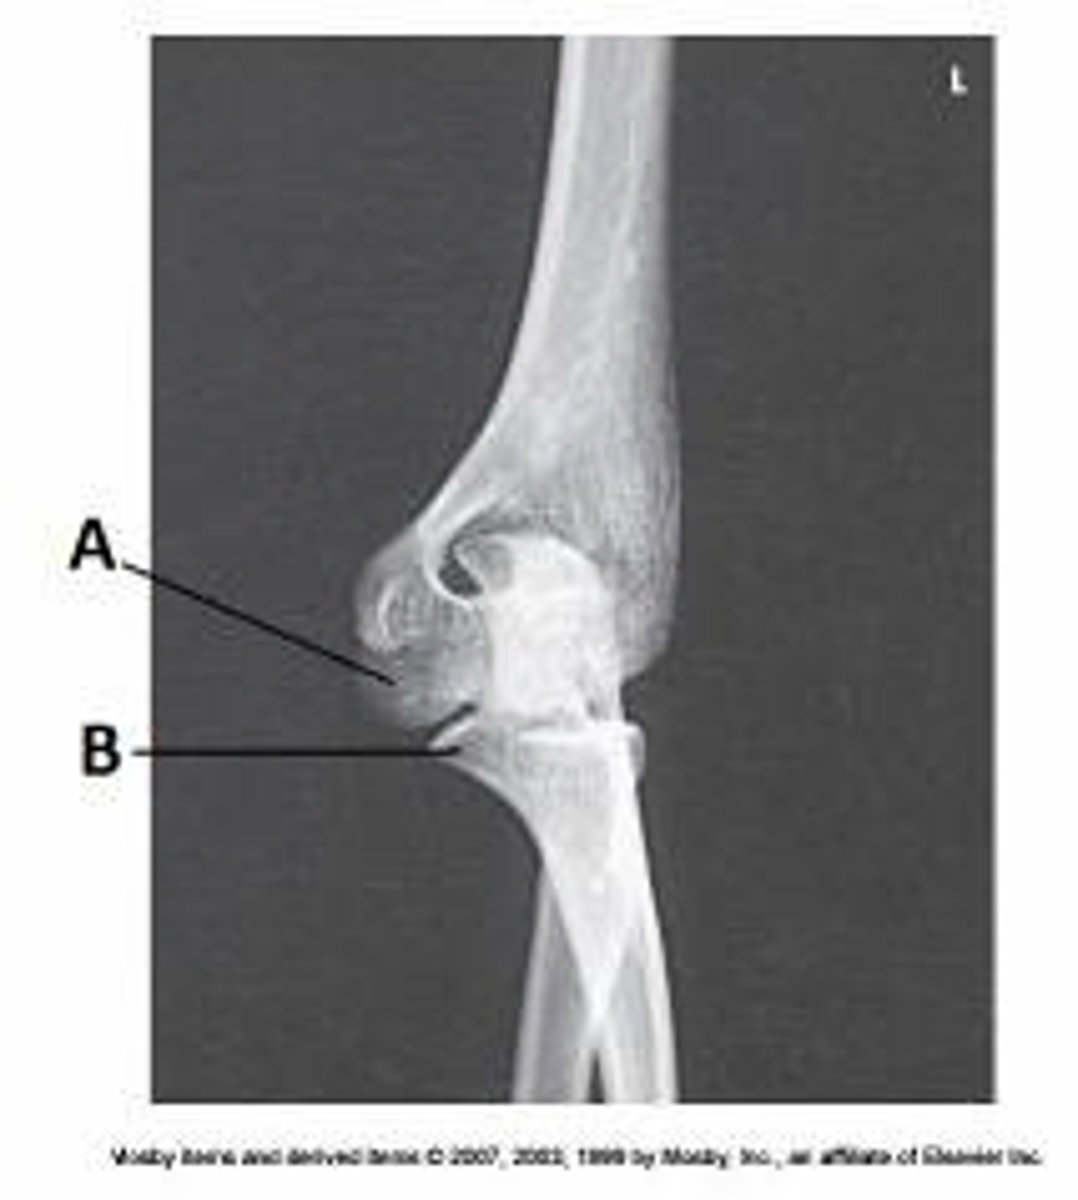

Capitulum

What anatomy is labeled as letter D in the image below?

Lateral epicondyle of the humerus

Medial epicondyle of the humerus

Trochlea

Coronoid process of ulna

What anatomy is labeled as letter B in the image below?

Lateral epicondyle of humerus